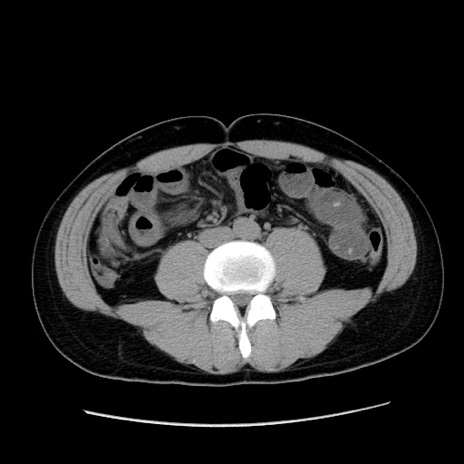

症例36(横断像)

【症例】20歳代 男性

【主訴】心窩部痛

【現病歴】今朝より上腹部痛あり。一旦軽快していたが再度出現したため救急要請。昨日夕に白身の魚を含む刺身を食べた。

【身体所見】BP 136/89mmHg、HR 74/min、BT 37.0℃、腹部:膨満、軟、心窩部に圧痛あり。反跳痛なし、筋性防御なし、腸雑音やや亢進あり。

【データ】WBC 17700、CRP 0.48